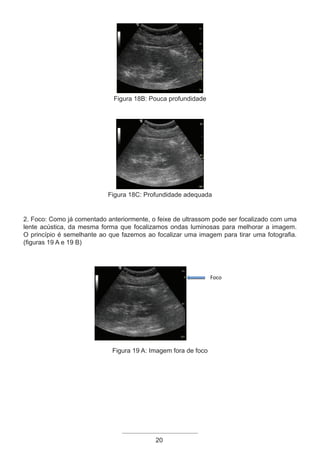

2. Foco: Como já comentado anteriormente, o feixe de ultrassom pode ser focalizado com uma

lente acústica, da mesma forma que focalizamos ondas luminosas para melhorar a imagem.

O princípio é semelhante ao que fazemos ao focalizar uma imagem para tirar uma fotografia.

(figuras 19 A e 19 B)

Figura 19 A: Imagem fora de foco